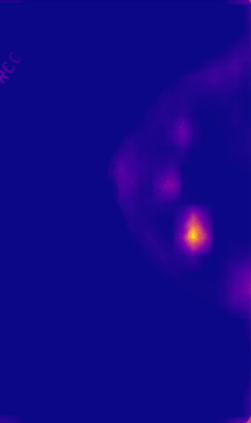

Breast cancer is the most widespread neoplasm among women and early detection of this disease is critical. Deep learning techniques have become of great interest to improve diagnostic performance. Nonetheless, discriminating between malignant and benign masses from whole mammograms remains challenging due to them being almost identical to an untrained eye and the region of interest (ROI) occupying a minuscule portion of the entire image. In this paper, we propose a framework, parameterized hypercomplex attention maps (PHAM), to overcome these problems. Specifically, we deploy an augmentation step based on computing attention maps. Then, the attention maps are used to condition the classification step by constructing a multi-dimensional input comprised of the original breast cancer image and the corresponding attention map. In this step, a parameterized hypercomplex neural network (PHNN) is employed to perform breast cancer classification. The framework offers two main advantages. First, attention maps provide critical information regarding the ROI and allow the neural model to concentrate on it. Second, the hypercomplex architecture has the ability to model local relations between input dimensions thanks to hypercomplex algebra rules, thus properly exploiting the information provided by the attention map. We demonstrate the efficacy of the proposed framework on both mammography images as well as histopathological ones, surpassing attention-based state-of-the-art networks and the real-valued counterpart of our method. The code of our work is available at https://github.com/elelo22/AttentionBCS.